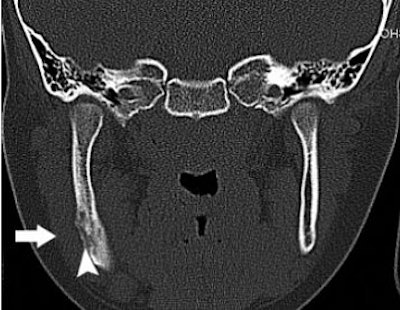

![]() |

| Coronal CT in a 7-year-old girl with sclerosing osteomyelitis demonstrates osseous sclerosis, remodeling, periosteal new bone (arrowhead), and soft-tissue swelling (arrow). Phal PM, Myall RWT, Assael LA, Weissman JL, "Imaging Findings of Bisphosphonate-Associated Osteonecrosis of the Jaws," American Journal of Neuroradiology, Vol. 28:6, pp 1139-1145. © American Society of Neuroradiology. |

Of the 15, all but one patient had orthopantomograms. Five patients had CT scans and one patient had a radionuclide bone scan. Nine patients underwent sequential imaging. All images were reviewed in consensus by two radiologists.

According to the imaging results, osseous sclerosis was the most commonly encountered x-ray finding in all 15 patients. In those who underwent sequential imaging, these sclerotic changes were often progressive, which can act as a hallmark for BRONJ, the authors stated. Osseous sclerosis "varied from subtle thickening of the lamina dura and alveolar crest to attenuated osteopetrosis-like sclerosis," they explained.

They also stated that they found CT more sensitive than orthopantomography for deciphering soft-tissue swelling, periosteal new bone, and sequestrum.